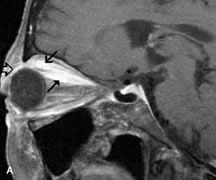

PATIENT PREPARATION Before MRI is performed, patients must be screened and prepared to avoid the potential hazards associated with the strong magnetic field. Patients who have ferrous aneurysm clips or cardiac pacemakers, who depend on life-support equipment, or who retain a possible metallic intraocular foreign body are not candidates for this imaging modality. MRI cannot be performed on obese patients who cannot fit into the bore of the magnet. Patients who are claustrophobic may not tolerate a prolonged period of study within the confines of the magnet, whereas others might do well if given a mild sedative. All worn metallic objects (e.g., necklaces, watches) should be taken off, credit cards set aside, and eye makeup removed before entering the room containing the magnet.5,20,34,35,36 NORMAL ORBITAL ANATOMY T1-weighted images provide the best anatomic details of the orbit because they display superior contrast resolution between normal structures (see Fig. 8). The vitreous has a long T1, resulting in an intermediate signal similar to brain, whereas the crystalline lens and sclera appear dark because of a longer T1 and short T2. The extraocular muscles, like all skeletal muscles, demonstrate a moderately long T1 and short T2 and highly contrast with the intense signal of the surrounding orbital fat (adipose tissue has an extremely short T1). The lacrimal glands appear as mottled areas of reduced intensity of the signal from the orbital fat in the lacrimal fossa. The optic nerves are seen with the same signal intensity as brain white matter and are hypointense relative to the orbital fat because their Tl is longer than the Tl of fat but shorter than the Tl of water. Cortical bone is not well delineated because it contains little free water, yielding minimal signal in MRI, and thus appears dark on all pulse sequences. This feature explains why MR images of the orbital apex and intracanalicular portion of the optic nerves are superior to comparable CT scans. Partial volume averaging of the bones in these regions obscures soft tissue details on CT images, whereas MRI reveals the signals only from the soft tissue structures with no cortical bone input. Bone marrow, on the other hand, is seen as a relatively intense signal because of its high fat content (see Fig. 8).37,38 T2-weighted pulse sequences are not ideal for imaging normal anatomy; however, they are particularly useful in revealing pathologic conditions (see Fig. 9). T2-weighted studies are most easily recognized by a bright vitreous signal. ORBITAL DISEASES Vascular Lesions Cavernous hemangiomas appear as well-circumscribed, smooth, usually intraconal masses that are isointense to muscle on T1-weighted images and hyperintense on T2-weighted images (Fig. 12). Patchy early enhancement is typically followed by diffuse, more homogeneous enhancement.39 The internal architecture of the mass, including septation and internal vasculature, may often be appreciated with high-quality orbital imaging.40 Lymphangiomas consist of ectatic vascular channels within a connective tissue stoma with varying degrees of lymphoid cellularity. On MRI, these tumors are typically poorly circumscribed, multicompartmental, and heterogeneous, often showing cystic dilations with fluid levels (Fig. 13). The signal characteristics within lymphangiomas vary considerably, reflecting cystic and solid components and the varying paramagnetic characteristics of blood at different stages of degradation.40–42 Acute hemorrhage appears hypointense on both T1- and T2-weighted formats. Methemoglobin present in subacute hemorrhage (3 to 14 days) leads to hyperintense signal on both T1- and T2-weighted images.41 A small percentage of lymphangiomas appear radiologically indistinct from orbital cavernous hemangiomas.43 Orbital varices are venous malformations that expand with increased systemic venous pressure, such as with Valsalva maneuvers. Because rapid acquisition of images during a Valsalva maneuver is important in imaging such a lesion, conventional or spiral CT is currently the modality of choice.44 MRI is an excellent modality for demonstrating enlargement of the cavernous sinus and dilation of the superior ophthalmic vein in patients with high-flow carotid-cavernous fistulas (Fig. 14).37MRA may be helpful in the evaluation of the venous outflow pattern. The rapidly flowing blood in these vascular structures carries the excited protons out of the section before they can be imaged, resulting in their dark appearance.5 In low-flow dural arteriovenous malformations, MRA may help define the arterial feeding vessels.45 Neural Lesions MRI is more effective than CT in delineating the intracranial optic nerves, chiasm, and optic tracts and, for this reason, is the preferred imaging modality in the evaluation of optic nerve disorders. The spatial relationships and image contrast of the orbital tissues with intraorbital optic nerve tumors is comparable between the two imaging modalities. The normal nerve is isointense to brain and appears enlarged and kinked owing to infiltration of an optic nerve glioma on T1-weighted images. Gliomas appear hyperintense on T2-weighted images and may be heterogeneous owing to cystic areas within the tumor. Contrast enhancement is variable.46 Intraorbital and intracranial optic nerve sheath meningiomas are usually isointense to cortical gray matter on Tl-weighted images and remain isointense on proton density studies (Fig. 15). Gd-DTPA is useful in delineating the intracranial extension of optic nerve meningiomas.7,47 The hyperostosis of bone and calcification associated with meningiomas are not demonstrated as well on MRI studies as on CT scans.20,37 Gd-DTPA–enhanced MRI also appears promising in the study of the permeability of the blood–brain barrier in selected optic neuropathies.22,48 MRI may reveal an enlarged optic nerve and some degree of contrast enhancement in cases of optic neuritis.49 Muscle Disorders Extraocular muscle enlargement in patients with thyroid-associated orbitopathy is demonstrated equally well with CT and MRI studies. However, the superior tissue contrast on MR images reveals better details of the relationships of the optic nerve to the thickened muscles at the orbital apex (Fig. 16).50 In addition, MRI may be able to differentiate between muscles that are enlarged as a result of edema and active inflammation and those enlarged because of fibrosis by their T2 relaxation times.21 Quantitative MRI was not found to be accurate in predicting the success of low-dose orbital irradiation.51 However, a muscular index relating the diameters of the rectus muscles to the bony orbital dimensions was useful in predicting optic nerve compression.52 MRI is also effective in imaging orbital tumors of mesenchymal origin, such as rhabdomyosarcoma, particularly in the assessment of extension into the anterior and middle cranial fossae (Fig. 17).37 The lack of any pathognomonic radiologic features necessitates rapid orbital biopsy when rhabdomyosarcoma is suspected. Osseous Lesions In general, CT is the imaging modality of choice when details of quantity and quality of bone are needed; however, abnormalities of bones can be detected indirectly by MRI. Cortical bone appears black (signal void) on MR images because of its low proton density and free-water content. The absence or discontinuity of the signal void of the orbital walls may represent bony destruction or fracture. Hyperostosis associated with prostate metastases or meningioma is visualized as areas of black smudging.50,53 Diseases in which the bone is replaced by pathologic tissues with a high free-water content, such as fibrous dysplasia, are well demonstrated on MRI. An intermediate signal intensity on T1-weighted images and hypointense signal on T2-weighted images is representative of fibrous dysplasia. Enhancement on post–Gd-DTPA MR scans is seen and is more evident in areas that are less mineralized.54 Cystic Lesions Dermoid cysts appear as rounded, well-defined lesions typically contiguous with an orbital bony suture. The high-intensity signal on T1-weighted images is attributed to the sebaceous-produced lipid contents (Fig. 18).31,50 Mucoceles may demonstrate a hypointense or hyperintense signal on MR images, depending on the concentration of proteinaceous or inflammatory fluid components. The integrity of the bony walls of the expanded sinus cavities cannot be assessed on MR as well as by CT.37,50,55,56 A high-signal intensity on Tl- and T2-weighted images is characteristic of orbital chronic hematic cysts because of the blood-breakdown products within the cysts.57 Trauma Although soft tissue relationships are usually better demonstrated on MRI, the evaluation of craniofacial bony trauma is preferable with CT. For example, prolapse of orbital fat through a fracture site and hemorrhage of adjacent tissues are demonstrated in an MR image, but the actual fractured bone is not imaged. Three-dimensional MRI of the orbit in subacute trauma has been described,58 although its precise role is not currently established. MRI has been suggested to be superior to CT in detecting intraorbital wooden foreign bodies.59,60 In a series of penetrating orbital injuries with organic foreign bodies, however, MRI was able to identify the foreign body in only four of seven cases.61 With an in vitro model for wood foreign body, McGuckin and colleagues concluded that CT was the imaging modality of choice.62 A careful history and, in selected cases, plain films to rule out a metallic foreign body are crucial before MRI is considered in patients with periocular trauma. MRI is particularly helpful in the detection and characterization of subperiosteal hematomas of the orbit (Fig. 19). They are most commonly seen in the subperiosteal space of the superior orbit as well-defined masses following a traumatic injury. The signal intensity varies depending on the acute, subacute, or chronic nature of the hematoma, based on the stage of blood degradation. Fresh hemorrhages are hypointense on T1-weighted images and hyperintense on T2 images. Hematomas that are 1 to 7 days old are hypointense on both T1- and T2-weighted images. T1-weighted images of hematomas more than a week old are hyperintense due to the oxidation of deoxyhemoglobin to methemoglobin, whereas the T2 images remain hypointense.63 Metastatic Tumors Breast carcinoma metastatic to the orbit has been demonstrated to be hypointense to the surrounding orbital fat on T1-weighted studies and hyperintense on T2-weighted images and has an affinity to the extraocular muscles (Fig. 20).50,64 The MRI characteristics of prostate carcinoma metastatic to the orbit have been described as involving the greater and lesser wing of the sphenoid, orbital roof, and optic canal. Diffuse bone hypertrophy with isointense or slightly hyperintense tissue on T1-weighted images represents the osteoblastic carcinomatous bone infiltration. Contrast enhancement is variable on T1-weighted and fat-suppressed images.65 Most other metastatic tumors also have a lower intensity signal on T1-weighted images and appear to displace or infiltrate normal orbital structures; however, their signal characteristics are variable on T2-weighted MR images.66 Many metastatic tumors demonstrate bright contrast enhancement with Gd-DTPA. Infectious Disorders MRI findings of preseptal and orbital cellulitis typically include increased signal intensities on T2-weighted images of the eyelids and orbital fat, respectively, due to the increased water content of the tissues. Since most cases of bacterial orbital cellulitis are associated with paranasal sinusitis, hyperintense signals of the affected sinuses may also be found on T2-weighted images as well as enhancement of polyps and granulation tissue on postgadolinium T1-weighted MR images. Subperiosteal abscess formation may occur due to contiguous spread of infection from the paranasal sinuses and appear on MRI as an area of intermediate signal on T1-weighted and proton-weighted MR images. The abscess may appear slightly hyperintense compared with muscle on T2-weighted scans with the necrotic contents having the greatest intensity.67 MRI and MRV are more sensitive than CT in revealing cavernous sinus thrombosis. Engorgement of the cavernous sinus, extraocular muscles, and ophthalmic veins is seen with hyperintensity of the thrombosed sinuses evident on all pulse sequences. The enlarged, thrombosed superior ophthalmic vein appears less hypointense than the normal contralateral ophthalmic vein, and hyperintensity within the lumen of the vessel may be seen on T1- and T2-weighted MR images.68 Inflammatory and Lymphoproliferative Lesions Inflammatory conditions of the orbit, both idiopathic (inflammatory pseudotumor) and those of known causes, have been found to be hypointense to fat and isointense to muscle on Tl-weighted studies and isointense or slightly hyperintense to fat on T2-weighted images (Fig. 21).50,64,69 The more fibrous or sclerosing varieties have less signal intensity on T2-weighted images. Marked enhancement is seen in pseudotumor infiltrates after gadolinium administration.70 The same signal characteristics are demonstrated in patients with Tolosa-Hunt syndrome, with mass lesions seen in the cavernous sinuses and orbital apices.71 Lymphomas have MRI characteristics similar to those of inflammatory lesions in that they are hypointense to fat and isointense to muscle on T1-weighted images (Fig. 22). They may appear hyperintense to fat on T2-weighted images, perhaps owing to less fibrosis than that seen in orbital inflammatory pseudotumor, although this is not a consistent finding.31,50,66 Lymphoid tumors typically enhance moderately after contrast injection. Unfortunately, studies have shown that tumor density and homogeneity are similar between inflammatory and malignant orbital infiltrates, and MRI cannot differentiate these lesions.72,73 Lacrimal Gland Tumors Lacrimal gland lesions present special problems in diagnosis and management. Pleomorphic adenoma (benign mixed tumor) should not be biopsied, but rather excised in toto. On the other hand, for lymphoma and inflammatory infiltrates, incisional biopsy is more appropriate than complete excision of the lacrimal gland. Thus, preoperative clinical and radiologic evaluation are especially crucial in planning appropriate surgical management. Pleomorphic adenomas demonstrate long T1 and T2 signal characteristics. They may show heterogeneity on T2-weighted images74 and moderate to marked enhancement with contrast.75 Signal characteristics of adenoid cystic carcinoma include hypointensity to fat on T1-weighted images, hyperintensity to fat with increased T2 weighting, and isointensity to fat on proton density-weighted studies (Fig. 23).31,75 Secondary bony alterations of the lacrimal fossa associated with lacrimal gland tumors, such as remodeling (benign mixed tumor) or destruction (adenoid cystic carcinoma), are seen indirectly on MR images; however, bone windows on CT scans provide better delineation of these changes. In contrast to the round or globular appearance of benign or malignant epithelial tumors of the lacrimal gland, lymphoproliferative tumors usually appear to be molding or draping onto the globe and the surrounding bony orbit. LACRIMAL DRAINAGE SYSTEM DISORDERS MRI with surface coils provides excellent spatial resolution and tissue-specific signal intensities of the lacrimal drainage system. These parameters have been found useful to more accurately demonstrate the extent of lesions in the lacrimal sac and differentiate long-standing mucoceles from solid tumors than CT.76 Physiologic studies in patients with tearing disorders now include MR dacryocystography, in which Gd-DTPA is either placed topically in the conjunctival fornix or injected by cannulation into the lacrimal sac. They provide a detailed morphologic and functional analysis of the lacrimal excretory system; however, they are no more sensitive than digital-subtraction dacryocystography or CT dacryocystography.77–79 INTRAOCULAR TUMORS On MRI, uveal melanomas have a typical appearance that helps to differentiate them from other primary and secondary intraocular tumors as well as choroidal detachments. Pigmented melanomas are hyperintense on Tl-weighted images, hypointense on T2-weighted studies, and hyperintense on proton density–weighted examinations (Fig. 24).30,31,50,80–82 These signal characteristics have been attributed to the paramagnetic properties of melanin because of stable free radicals that shorten the T1 and T2 relaxation times. Moderate enhancement is seen on postgadolinium T2-weighted images. Gadolinium-enhanced T1-weighted images are particularly sensitive in detecting choroidal melanomas.83 MRI may be less sensitive in detecting extrascleral extension of tumor than echography performed by an experienced ultrasonographer.84 Tumors metastatic to the choroid are hyperintense on T1- and T2-weighted images.24 The signal characteristics, however, may be similar to those seen with choroidal melanoma. Choroidal hemangiomas, on the other hand, have an intermediate signal on T1-weighted sequences and become hyperintense on T2-weighted images50 as well as proton density–weighted images.81 Retinoblastomas display moderate signal intensity on T1-weighted studies and a low signal on T2-weighted images.31,80,85 Calcification can be easily detected by CT and ocular ultrasonography but is not imaged by MRI.25,50 The presence of optic nerve involvement is best evaluated by MRI. ACQUIRED ANOPHTHALMIA When an eye is removed owing to tumor or trauma, an implant is typically placed in the intraconal space. MRI may be useful in defining the size, shape, and position of such orbital implants.86 Porous hydroxyapatite or polyethylene implants are preferred by many surgeons performing enucleation or evisceration. A porous implant offers the possibility of supporting a motility coupling peg to increase the movement of the overlying prosthesis. MRI with contrast is used by some surgeons to evaluate the degree of fibrovascular ingrowth in hydroxyapatite87 and porous polyethylene88 implants prior to motility peg placement. |